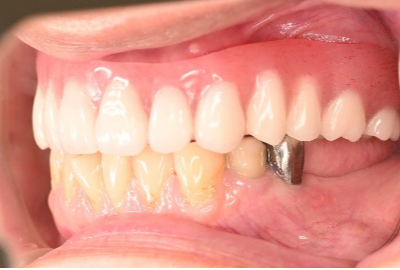

Before

After

【義歯を装着したところ】

【義歯を外したところ】

マグネット式総入れ歯

緑丸は組み込まれたマグネット